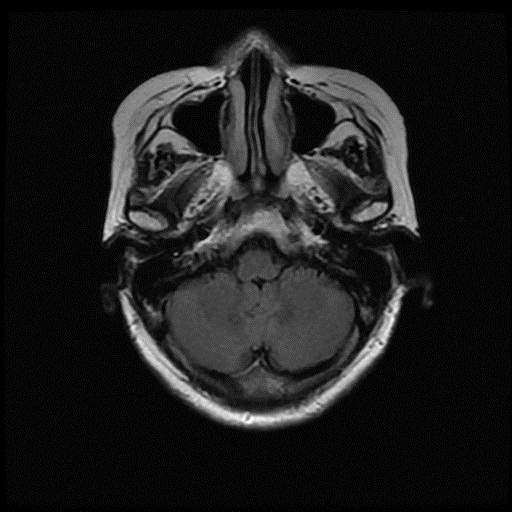

ËÀ´°ïÎÒ¿´¿´Õâ¸öÄÔ²¿CTµÄÄÔ¼¹Òº°üÀ¨ÄÄЩ£¿ ÎÒÏëÓÃImagej²âÁ¿Ò»ÏÂÃæ»ý¡£